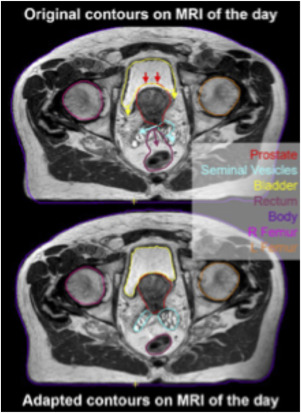

MRI-guided adaptive radiotherapy for liver tumours: visualising the future.

Lancet Oncol. 21: e74-e82Bohoudi O. Bruynzeel A.M.E. Senan S. et al.

Fast and robust online adaptive planning in stereotactic MR-guided adaptive radiation therapy (SMART) for pancreatic cancer.

Radiother Oncol. 125: 439-444Green O.L. Henke L.E. Hugo G.D.

Practical Clinical Workflows for Online and Offline Adaptive Radiation Therapy.

Semin Radiat Oncol. 29: 219-227Mittauer K. Paliwal B. Hill P. et al.

A New Era of Image Guidance with Magnetic Resonance-guided Radiation Therapy for Abdominal and Thoracic Malignancies.

Cureus. 10: e2422Rosenberg S.A. Henke L.E. Shaverdian N. et al.

A Multi-Institutional Experience of MR-Guided Liver Stereotactic Body Radiation Therapy.

Adv Radiat Oncol. 4: 142-149Feldman A.M. Modh A. Glide-Hurst C. et al.

Real-time Magnetic Resonance-guided Liver Stereotactic Body Radiation Therapy: An Institutional Report Using a Magnetic Resonance-Linac System.

Cureus. 11: e5774Henke L.E. Olsen J.R. Contreras J.A. et al.

Stereotactic MR-Guided Online Adaptive Radiation Therapy (SMART) for Ultracentral Thorax Malignancies: Results of a Phase 1 Trial.